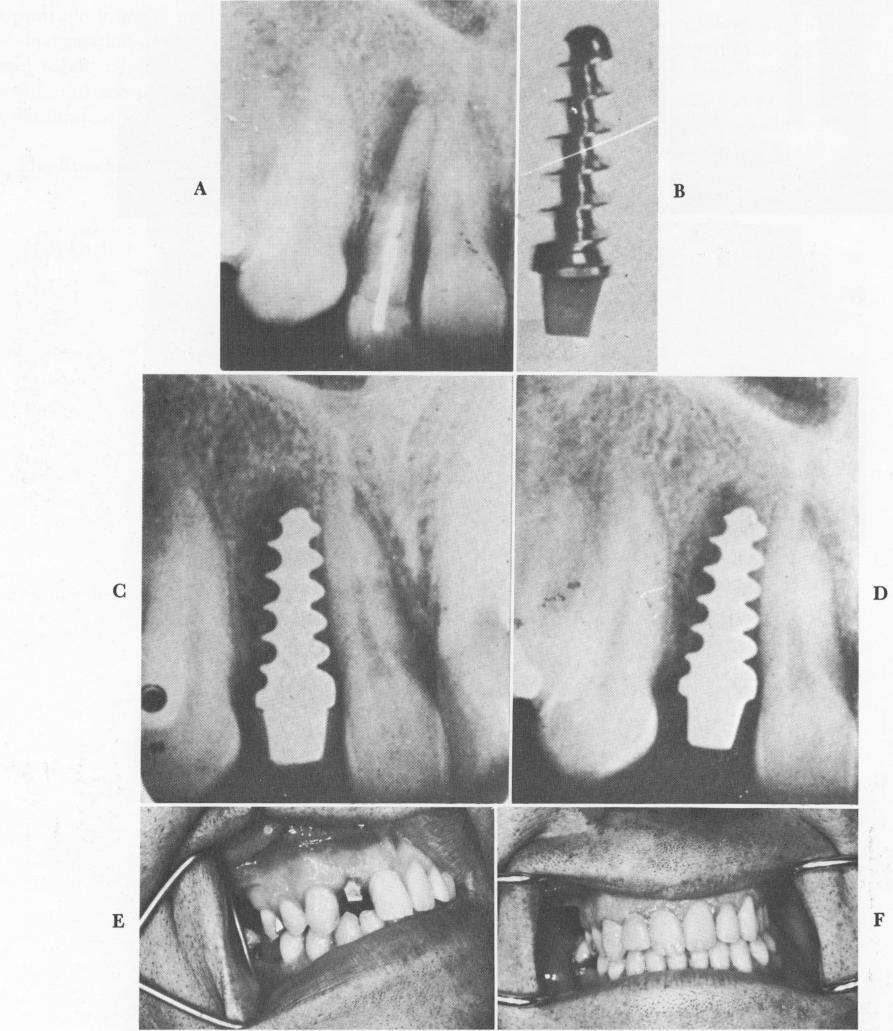

Fig. 5-9. Here the Strocks limited their chances of success by choosing to do an implantation in a diseased site, A. The screw, B, was inserted into the site. Roentgenograms, C and D, show little bone regrowth, although the "tooth," E and F, appeared to be firm. (From Strock, A. E.: Experimental work on a method for replacement of missing teeth by direct implantation of a metal support into the alveolus, Amer. J. Orthodont. 25:467-472, 1939.)

1 Strock endosseous implant placed in diseased site in maxilla